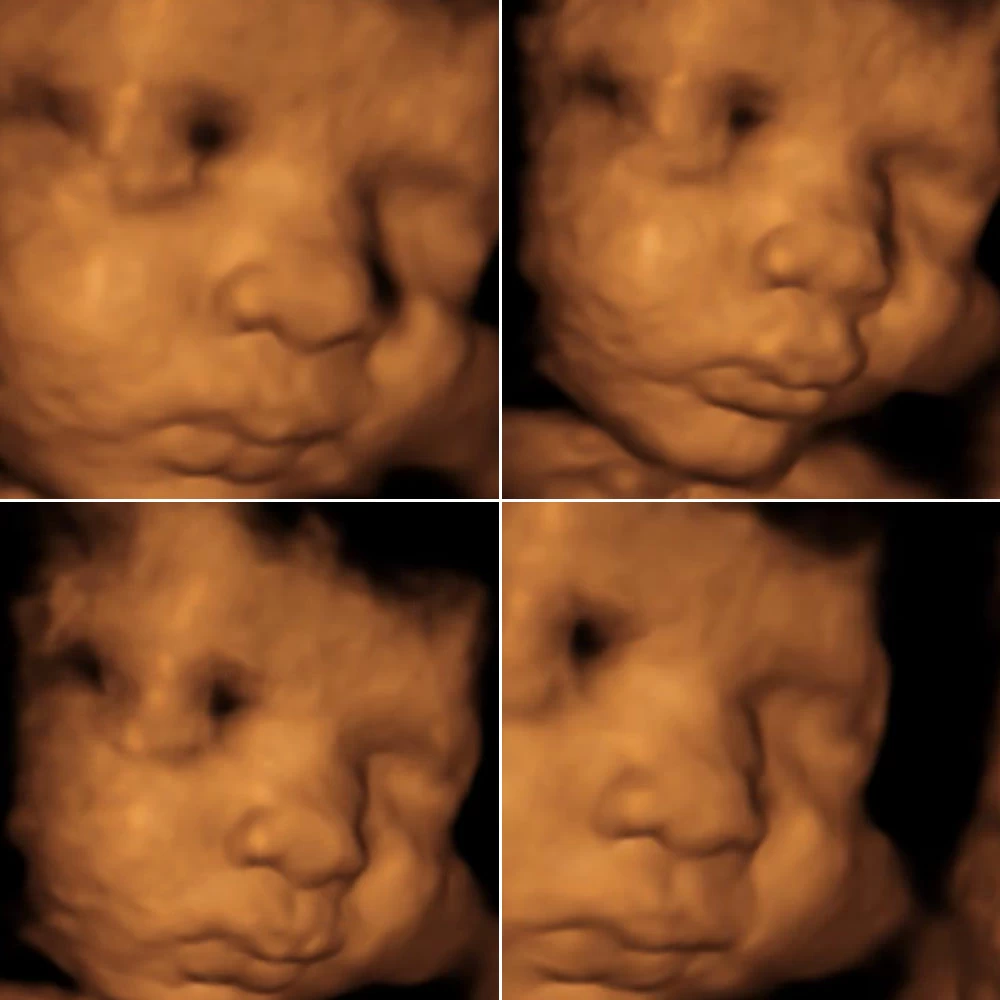

Самая точная УЗ-диагностика с помощью аппаратов премиум-серии